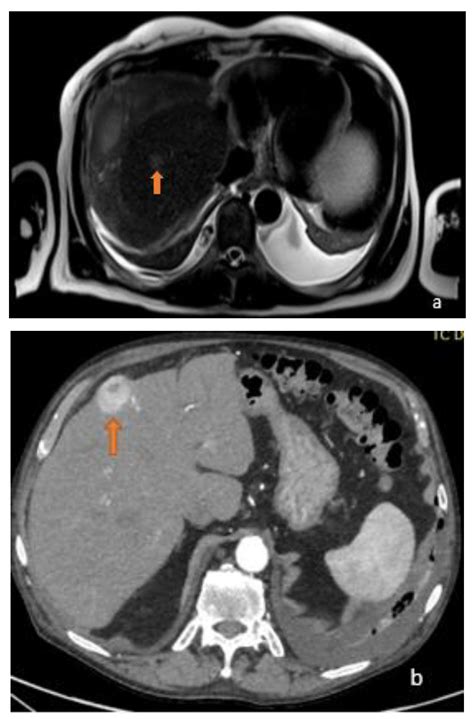

• Detailed Imaging: A dedicated liver protocol CT scan or an MRI with liver-specific contrast agents can provide high-resolution details about the lesion’s blood supply and cellular structure.

Distinguishing Between Benign and Malignant Lesions

When a doctor identifies a lesion on liver, the diagnostic process aims to rule out malignancy. Malignant lesions can be either primary (starting in the liver, such as hepatocellular carcinoma) or secondary (metastatic, meaning cancer that spread from another organ like the colon, breast, or lung). The following table summarizes key differences often evaluated by medical professionals.